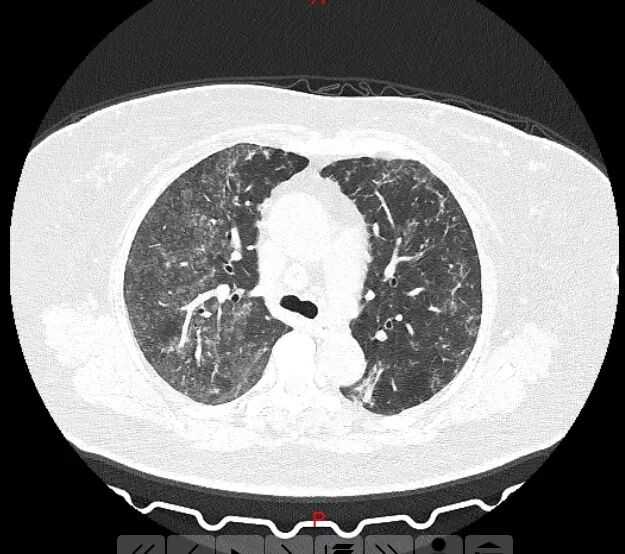

近日,杭州两名女子纷纷检查出肺部呈毛玻璃影,难道是新冠肺炎?据调查,两名女子一直居家隔离,没有外出迹象,也没有武汉接触史。这是为什么呢?

经过权威医院诊断表明:是因为84消毒液引起的过敏性肺泡炎!